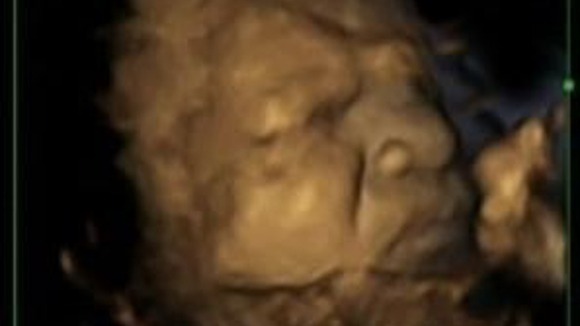

Unborn Babies learn & practice to grimace in the womb

Unborn babies “practice” facial expressions of pain while they are in the womb, scientists say.

Foetuses have been pictured using 4D scanning technology showing what appears to be pain.

The researchers, from Durham and Lancaster universities, suggest the ability to grimace is a “developmental process” which could help doctors assess the health of a foetus.

The study, published in the journal Plos One, found when the mother was 24 weeks pregnant, unborn babies were able to make simple expressions such as smiling. By 36 weeks the children were able to create “complex multi-dimensional expressions” such as pain.

Researchers, who examined video footage of 4D scans of 15 healthybabies, said the process was “adaptive” and helped the unborn baby to prepare for life after birth.

The study expands on previous research that suggests facial expressions of healthy foetuses develop and become more complex during pregnancy.

Researchers hope further investigation will examine whether the development of facial expressions in the womb is delayed if the mother smokes or drinks during pregnancy.

Lead researcher Dr Nadja Reissland, of Durham University’s Department of Psychology, said: “It is vital for infants to be able to show pain as soon as they are born so that they can communicate any distress or pain they might feel to their carers and our results show that healthy foetuses ‘learn’ to combine the necessary facial movements before they are born.

“This suggests that we can determine the normal development of facial movements and potentially identify abnormal development too. This could then provide a further medical indication of the health of the unborn baby.

“It is not yet clear whether foetuses can actually feel pain, nor do we know whether facial expressions relate to how they feel. Our research indicates that the expression of foetal facial movements is a developmental process which seems to be related to brain maturation rather than being linked to feelings.”